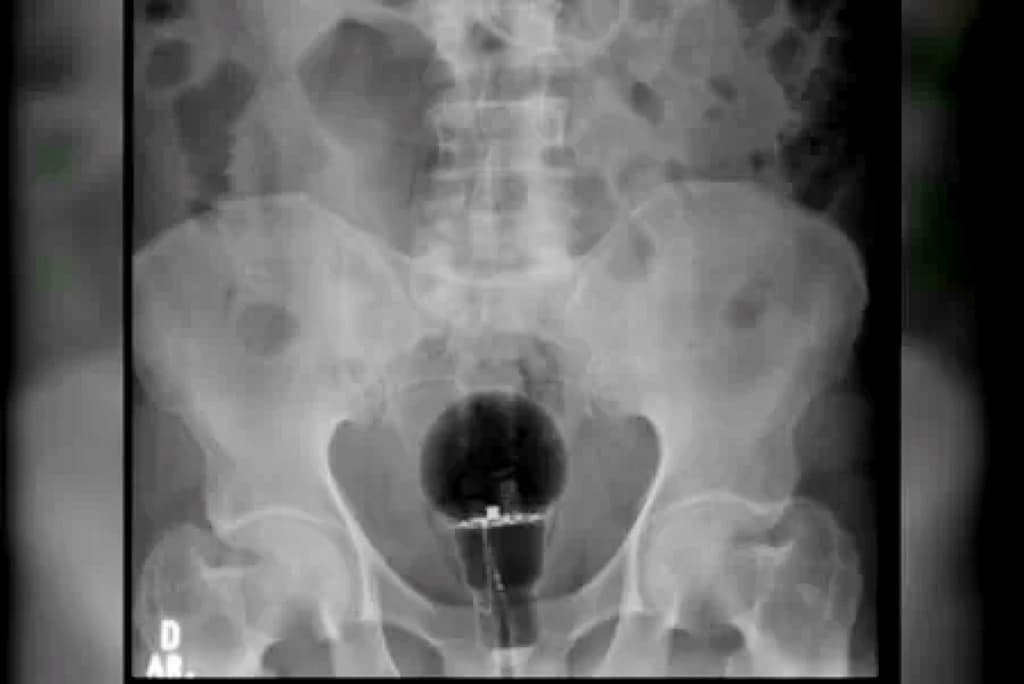

Um homem colombiano de 53 anos chegou a um hospital do país com dores intensas em março último. Aos médicos, o paciente disse não saber do que se tratava. No entanto, exames de imagem mostraram que uma lâmpada foi enfiada em seu reto.

“O objeto não era palpável ao toque”, afirmou o gastroenterologista Julian Pylori, que fez o atendimento, em um tweet. O médico usa as redes sociais com frequência para compartilhar atendimentos inusitados.

Objetos como este, que correm o risco de se quebrar, tem de ser retirados do corpo em procedimentos cirúrgicos. No entanto, segundo reportagem da TV Azteca, foi possível succionar a lâmpada porque ela era feita de plástico.